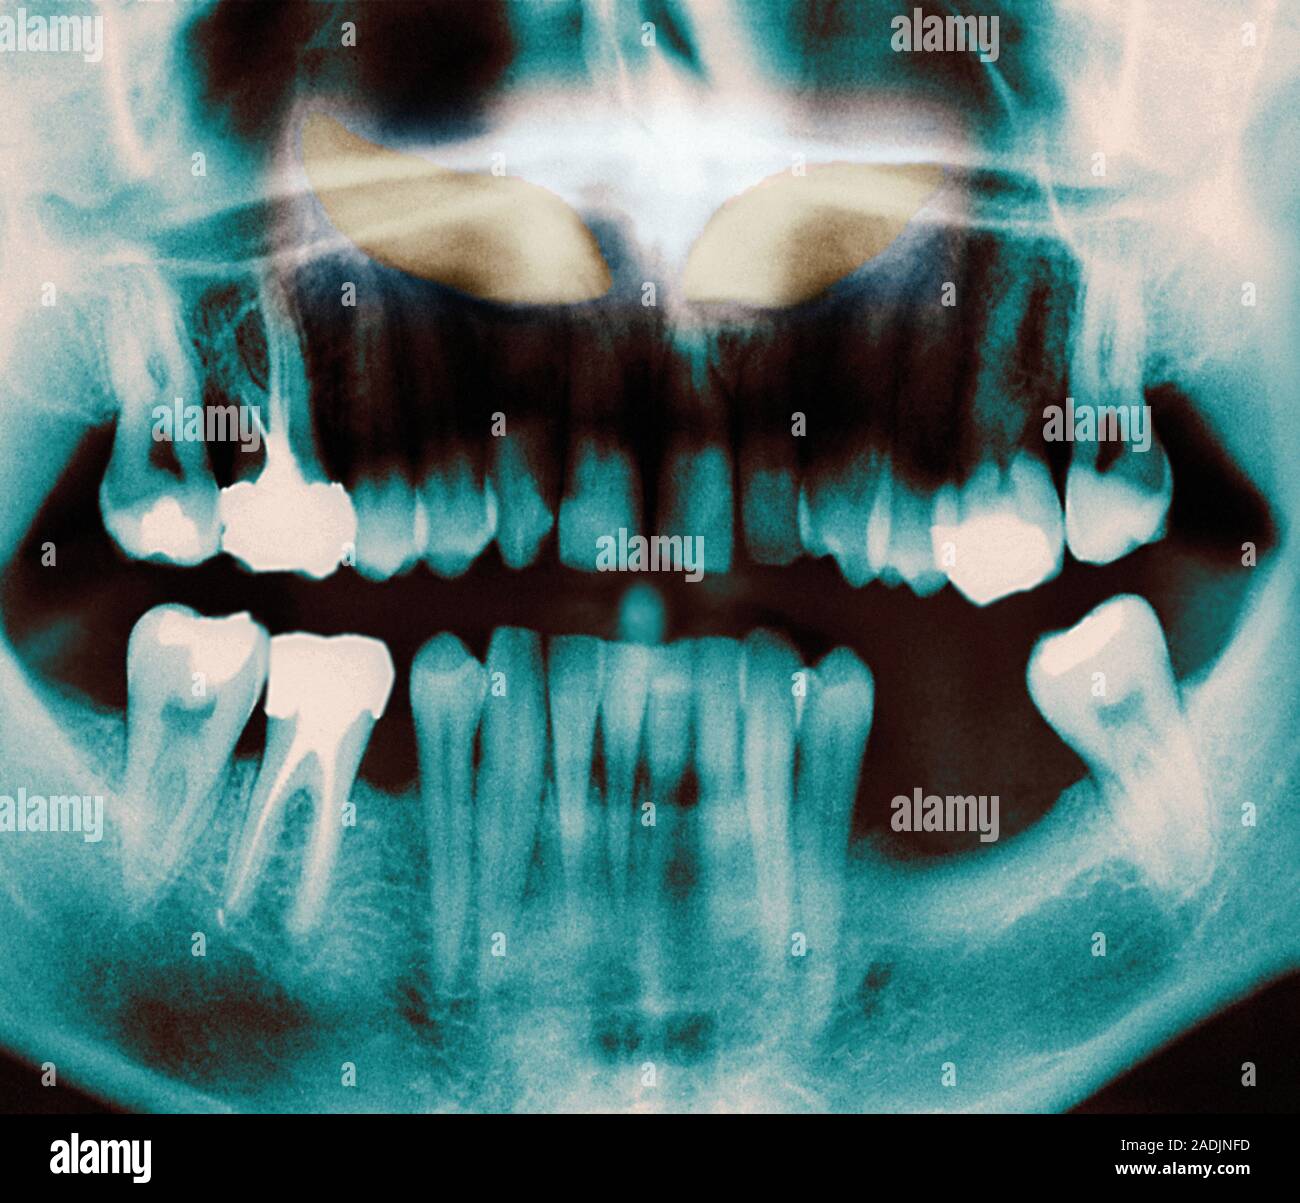

From www.alamy.com

Impacted incisors. Coloured dental Xray of impacted incisors (yellow). Impacted teeth are those Dental Block Ed the transient duration of regional analgesia has prompted concerns that treated patients may be more likely to return to the ed. Dental fractures with visible exposed pulp should be treated by capping (covering the exposed pulp) with calcium hydroxide in the ed. an oral nerve block is a simple and effective way to manage orofacial pain without distorting. Dental Block Ed.